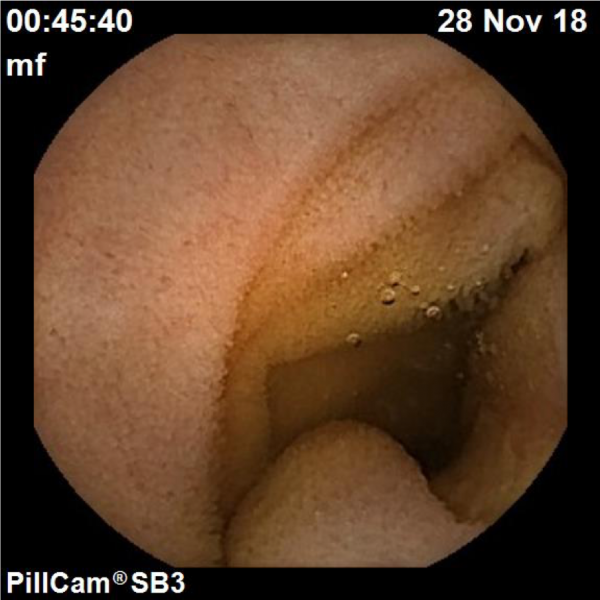

A sneaky ileal diverticulum

Fotografia